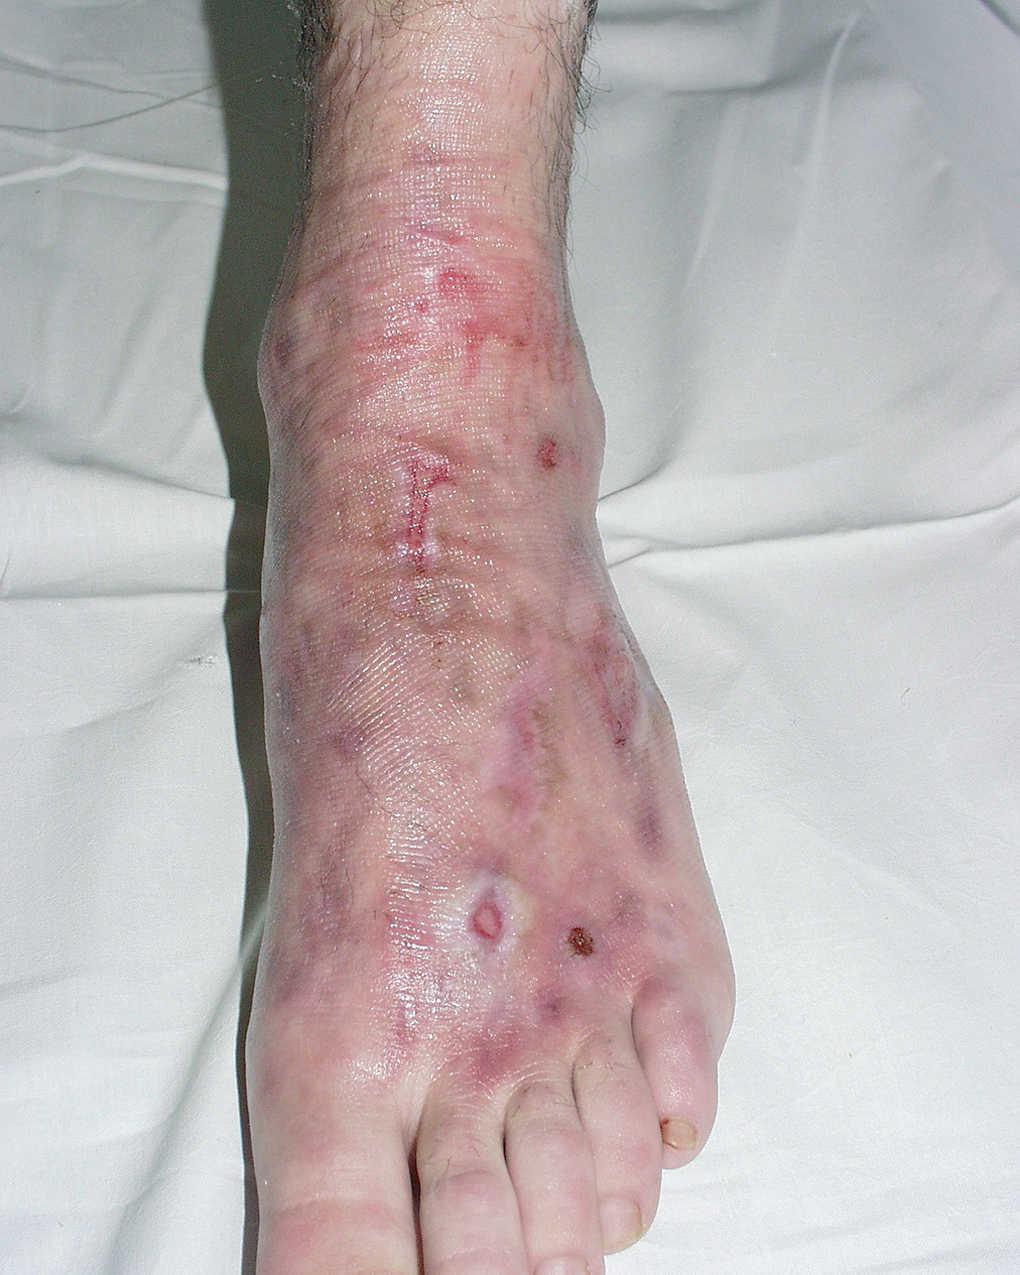

Al inicio del cuadro doloroso el paciente refería hinchazón, color violáceo y piel fría en el dorso del pie afectado y unas semanas después aparecieron erosiones de morfología lineal (fig. 1). Una biopsia cutánea fue inespecífica y un estudio de inmunidad con anticuerpos antinucleares dio resultados negativos. Se consideró que estas lesiones cutáneas estaban asociadas a ASR.

Fig. 1.--Coloración eritematosa violácea en el dorso del pie izquerdo, con edema y úlceras superficiales lineales y otras ovaladas.

La ASR se acompaña, de forma habitual, de alteraciones cutáneas que consisten principalmente en edema, inestabilidad vascular, cambios en la temperatura y el color de la piel, alteraciones en el crecimiento del pelo y las uñas y en las fases finales puede aparecer atrofia cutánea 4-6. Nuestro paciente presentaba úlceras superficiales de morfología lineal, edema y cianosis. Webster publicó 2 casos de ASR con lesiones similares 1. Sundaram encontró úlceras cutáneas en un 12 % de una serie de 26 pacientes con ASR 4 y van der Laan, en una serie de 154 pacientes diagnosticados de ASR, observó que 26 de ellos desarrollaban úlceras cutáneas 3.

En los pacientes con ASR y úlceras cutáneas crónicas se sospecha habitualmente un proceso de automutilación 1,3,7 por la morfología de las lesiones que suele ser lineal, en zonas accesibles al paciente y por la mala respuesta a los tratamientos convencionales. Sin embargo, las series de pacientes descritos con lesiones similares apuntan a un mecanismo subyacente común que sería la fragilidad cutánea que aparece en los estadios finales de la ASR, así como una respuesta inusual ante un traumatismo mínimo por alteraciones en los sistemas nervioso y vascular encargados de mantener la integridad cutánea.